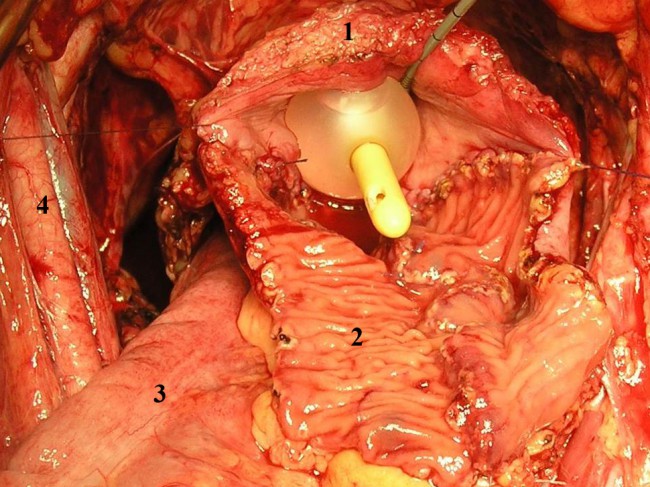

При сохранении тазового дна и выполнении континентной деривации мочи с формированием ортотопически дислоцируемого мочевого резервуара на проксимальный конец резецированной уретры накладывали 6 провизорных лигатур атравматическим монофиламентым шовным материалом (3/0) на 1, 3, 5, 7, 9, 11 часах условного циферблата (рис. 1).

Рис. 1. Провизорные лигатуры на мембранозном отделе уретры (А). Б – Катетер Фолея, заведенный в уретру.